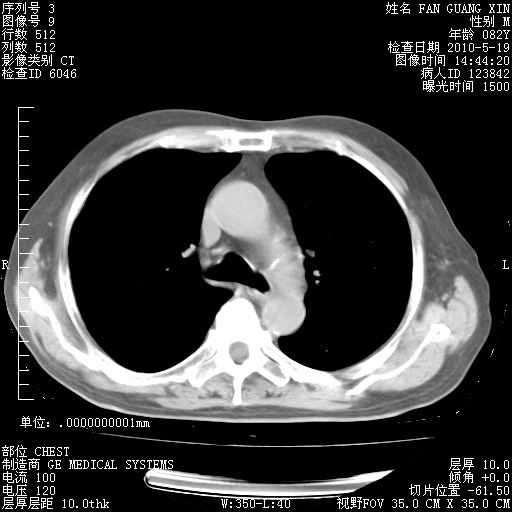

可改为口服强的松40-50mg/d治疗,若病情仍稳定,胸部阴影不再吸收可逐渐减量